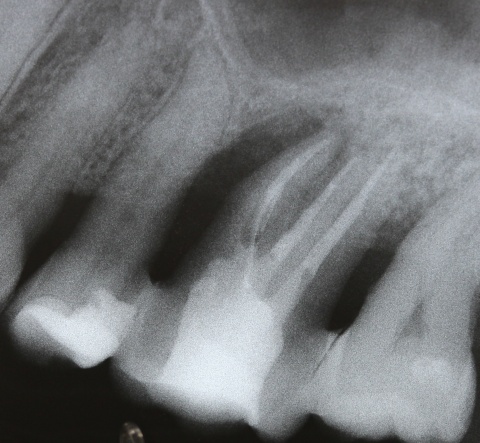

Ziel ist es, durch die Entfernung von Gewebs- und/oder Zahnanteilen die Zugänglichkeit zu schwer zugänglichen parodontalen Defekten zu verbessern. Darüber hinaus kann durch diese Maßnahmen die Hygienefähigkeit verbessert und eine Neubesiedelung des Parodontiums durch die mikrobielle Plaque verhindert werden. Vor allem die Prognose von furkationsbeteiligten Molaren kann auf diese Weise deutlich verbessert werden. In einer vielbeachteten Studie aus dem Jahre 2001 haben Fugazotto und Mitarbeiter die Prognose von 701 resektiv behandelten Molaren untersucht und beeindruckende Ergebnisse erzielt. Nach 15 Jahren waren noch 678 Molaren (94,9 %) in situ und erfüllten die vorgegebenen Erfolgskriterien. So lautete dann auch die Kernaussage dieser Studie, dass bei richtiger Indikationsstellung resektiv behandelte Molaren mindestens die gleich gute Langzeitprognose wie Implantate haben. In diesem Zusammenhang sei erwähnt, dass die Voraussetzung für eine erfolgreiche resektive Therapie die erfolgreiche endodontische Behandlung ist. Wie später noch ausgeführt wird, haben sich gerade auf diesem Gebiet durch technische Neuerungen völlig neue Möglichkeiten ergeben, was die Prognose der resektiv behandelten Molaren weiter verbessern dürfte. Ein kleines Beispiel, wie durch derartige Behandlungsschritte eine Implantation verhindert werden kann, zeigen die Abb. 5 und 6, wo durch eine Hemisektion des mesialen Wurzelanteils am Zahn 46 und anschließende Versorgung mit einer kleinen Brücke von 45 auf 46 eine Implantatinkorporation unnötig wurde.